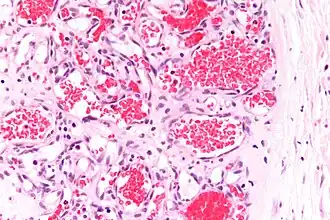

Capillary hemangioma

Strawberry naevus, H&E stain

The majority of IHs can be diagnosed by history and physical examination.[32] In rare cases, imaging (ultrasound with Doppler, magnetic resonance imaging), and/or cytology or histopathology are needed to confirm the diagnosis.[33][34] IHs are usually absent at birth or a small area of pallor, telangiectasias, or duskiness may be seen. A fully formed mass at birth usually indicates a different diagnosis. Superficial hemangiomas in the upper dermis have a bright-red strawberry color, whereas those in the deep dermis and subcutis, deep hemangiomas, may appear blue and be firm or rubbery on palpation. Mixed hemangiomas can have both features.[32] A minimally proliferative IH is an uncommon type that presents with fine macular telangiectasias with an occasional bright-red, papular, proliferative component. Minimally proliferative IHs are more common in the lower body.[35]

A precise history of the growth characteristics of the IH can be very helpful in making the diagnosis. In the first 4 to 8 weeks of life, IHs grow rapidly with primarily volumetric rather than radial growth. This is usually followed by a period of slower growth that can last 6–9 months, with 80% of the growth completed by 3 months. Finally, IHs involute over a period of years.[36] The exceptions to these growth characteristics include minimally proliferative His, which do not substantially proliferate[35] and large, deep IHs in which noticeable growth starts later and lasts longer.[36] If the diagnosis is not clear based on physical examination and growth history (most often in deep hemangiomas with little cutaneous involvement), then either imaging or histopathology can help confirm the diagnosis.[33][37] On Doppler ultrasound, an IH in the proliferative phase appears as a high-flow, soft-tissue mass usually without direct arteriovenous shunting. On MRI, IHs show a well-circumscribed lesion with intermediate and increased signal intensity on T1- and T2-weighted sequences, respectively, and strong enhancement after gadolinium injections, with fast-flow vessels.[33] Tissue for diagnosis can be obtained via fine-needle aspiration, skin biopsy, or excisional biopsy.[38] Under the microscope, IHs are unencapsulated aggregates of closely packed, thin-walled capillaries, usually with endothelial lining. Blood-filled vessels are separated by scant connective tissue. Their lumina may be thrombosed and organized. Hemosiderin pigment deposition due to vessel rupture may be observed.[39] The GLUT-1 histochemical marker can be helpful in distinguishing IHs from other items on the differential diagnosis, such as vascular malformations.[34]